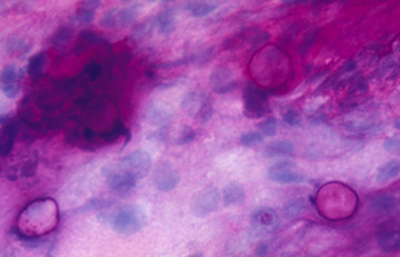

Las coloraciones empleadas en extendidos corneales para visualizar los quistes y trofozoitos de Acanthamoebas usando métodos sencillos son múltiples, siendo las que nos parecen más recomendables las coloraciones de Giemsa y el Acido Periódico de Schiff (PAS), (Figura 33 y 34) ambas usuales en los laboratorios de patología.

Fig. 33 PAS, Original x250

Fig. 34 PAS, Original x160